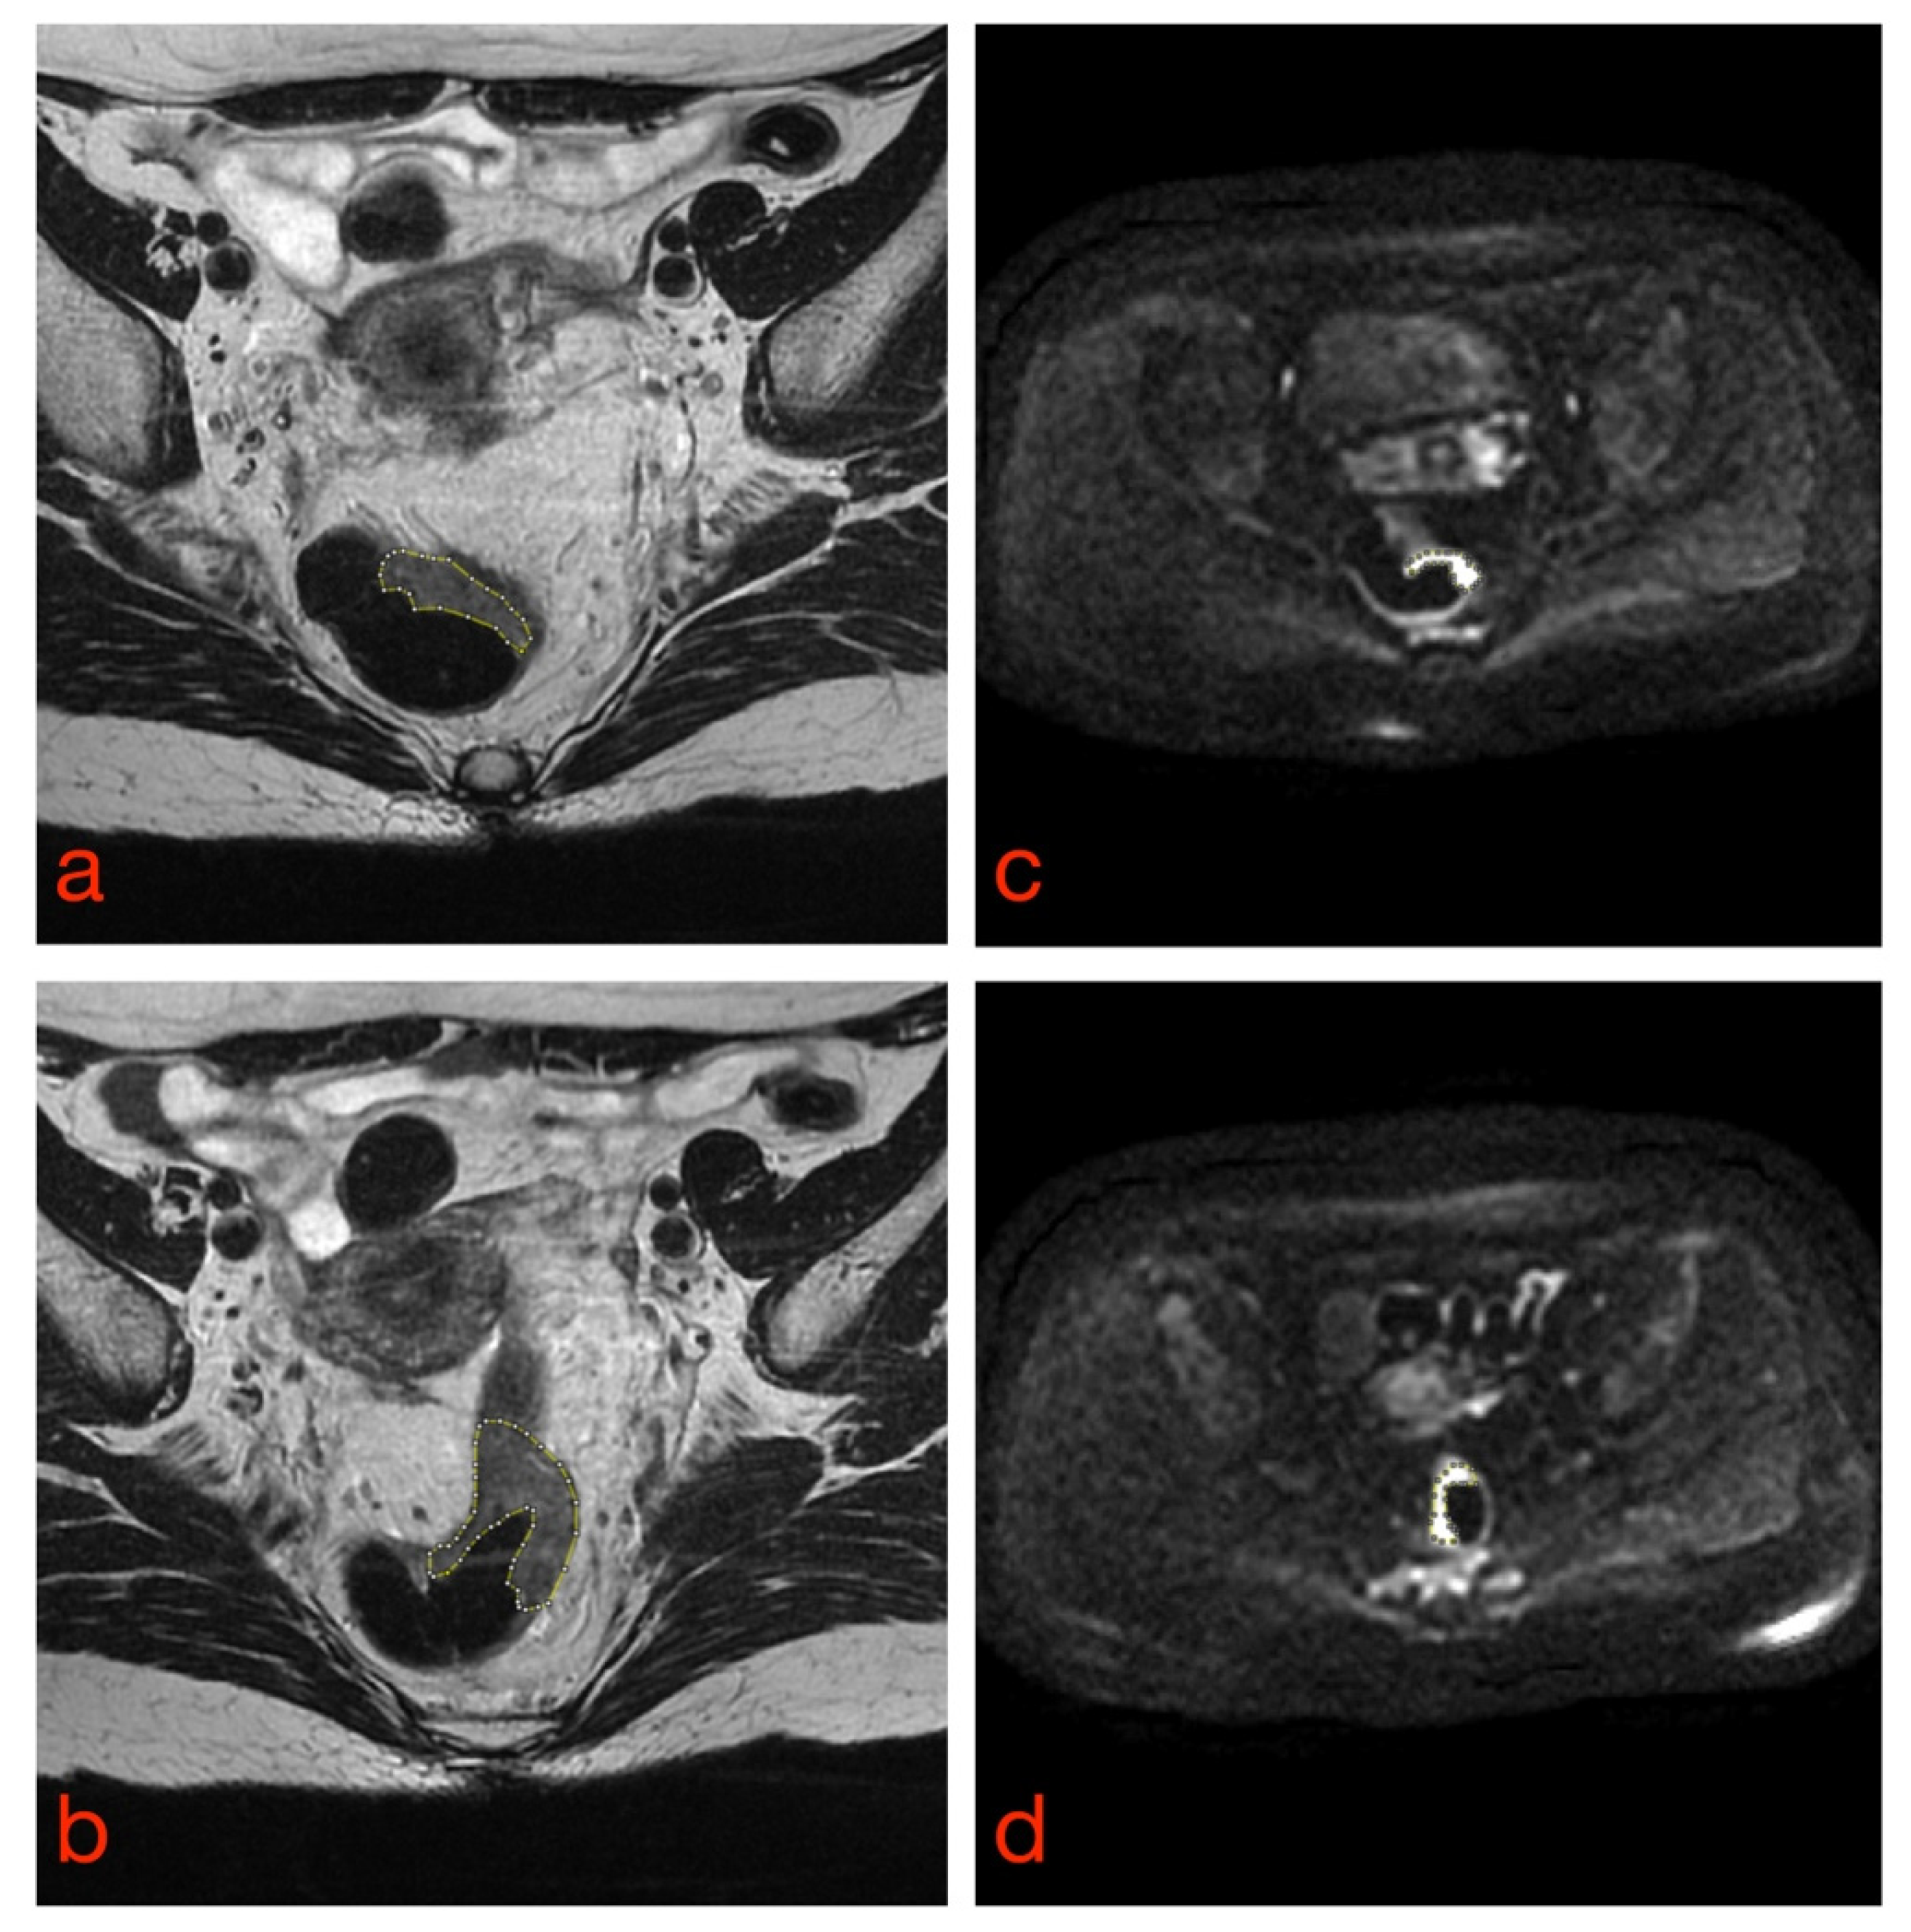

Once all image datasets have been acquired, the tissues of interest must be outlined by tracing regions of interest (ROIs) inside or around them to differentiate them from neighboring structures (e.g., tumor vs. normal tissue) (Figure 2). This task is called segmentation and can be manual, semiautomatic or fully automatic. Manual and semiautomatic methods are time-consuming tasks, hence difficult to implement in daily radiological and clinical practice; they also suffer from high intra- and interobserver variability [20]. Several studies have demonstrated that differences among segmentations can strongly affect the values of radiomics features and, consequently, the robustness of the radiomics model [36,37,38]. Therefore, when developing classifiers based on segmentation of ROIs, it is essential to determine the variability of radiomics features concerning the tumor delineation process and to implement the appropriate strategies to deal with this issue, e.g., by eliminating those features whose variability is higher than their prognostic value.

Figure 2. Manual tumor segmentation from T2-weighted (a,b) and DW (c,d) rectal MR images. Tumor borders are highlighted as dashed lines.